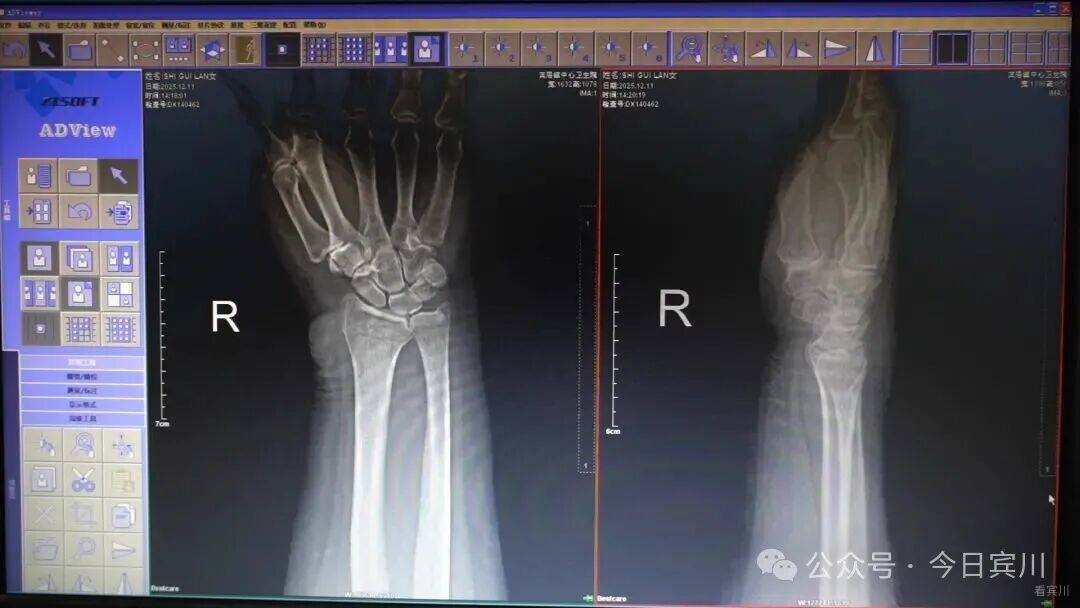

“有分院患者需诊断。”提示音响起,宾川县医疗集团影像诊断中心医师迅速打开由宾居镇中心卫生院传来的数字X光片。统一阅片、出具报告、反馈结果,全程不超过十分钟。

乡镇卫生院传来的片子,我们都优先处理,一般情况下,5—10分钟回传给他们结果。

依托统一管理的资源中心,宾川建立起“影像一张片、检验一把尺、心电一张网”的互认体系,253项检查检验结果在县域内互通互认。自2024年8月实施以来,已累计执行检查检验结果互认4200次,为患者节省费用37.7万元。